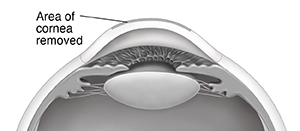

PRK (photorefractive keratectomy) is a procedure to reshape the cornea. It may help you see better without glasses or corrective lenses. This method uses an excimer laser. This laser makes a concentrated beam of ultraviolet (UV) light. Each pulse of the laser can remove a tiny part of the cornea. PRK can be used to treat the following:

A small surgical tool, an alcohol solution, or the laser is used to remove the surface of the central part of your cornea (the epithelium). Laser treatment lasts for 10 to 90 seconds.